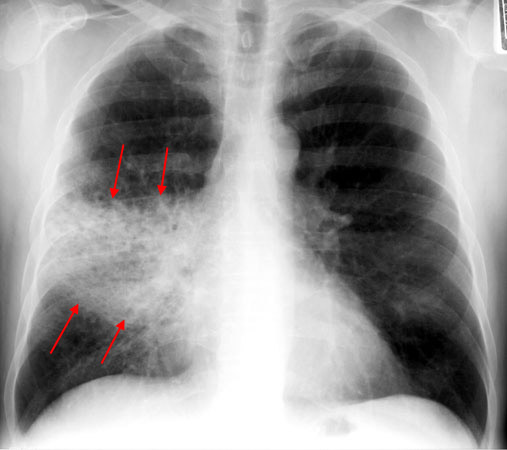

Pneumonia with Streptococcus pneumoniae | Allergy and Clinical

Chest Radiology